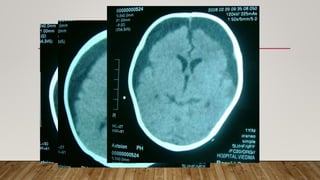

INDICACIONES DE IMÁGENES

• No de rutina

• Para descartar complicaciones: abscesos,

ventriculitis, infartos, empiema, hidrocefalia,

trombosis

• Signos neurologicos focales persistentes

• Cultivos LCR + persistentes

• Aumento polimorfonucleares persistente

luego 10 dias terapia

• Meningitis recurrente